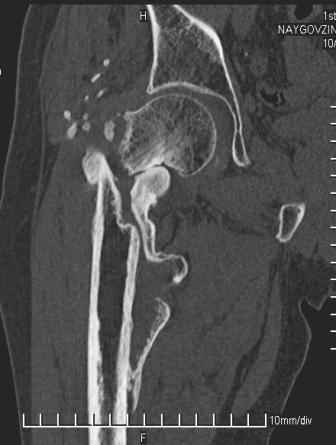

Больной Н. 44 года травма 1,5 года назад июнь 2008 года чрез-под вертельный перелом правого бедра. Во время лечения у больного развился алк. делирий, проводилось консервативное лечение перелома.

Беспокоят боли, укорочение конечности.Укорочение 3 см. Ногу поднимает, сгибание ограничено, ротационные движения в полном объеме.На КТ перелом сросся за счет костной мозоли.Что делать?

Уважаемый Глеб! Укорочение наверное побольше, да и наружно-ротационная установка скорее всего присутствует. Суставная щель прекрасная, головка живее всех живых. Ратую за подвертельную с латерализацией: исключает нарушение механической оси («исключает вальгус в коленe»), максимально удлиняет без натяжения m.iliacus. Для иллюстрации остеотомия-переделка (слава богу не автопеределка) у мужчины 65 лет.